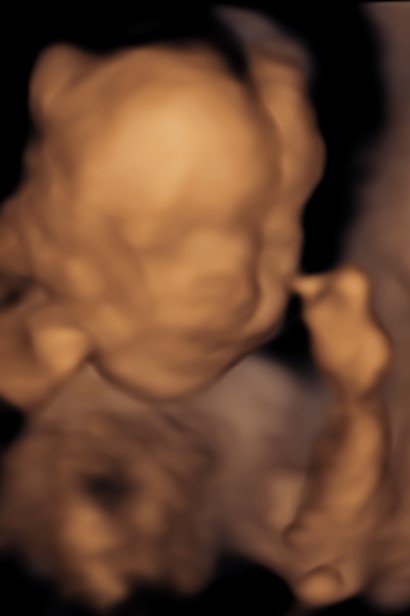

Monmouth County’s First 4D/5D/HD Live Ultrasound Studio

4D/5D/HD Ultrasound Gallery

Gallery